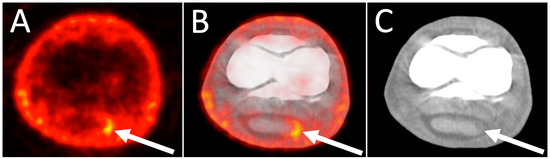

4.1. 18F-NaF PET as 3D Bone Scans of the Distal Equine Limb

4.2. 18F-NaF PET Combined with CT or MRI for Optimal Bone Imaging